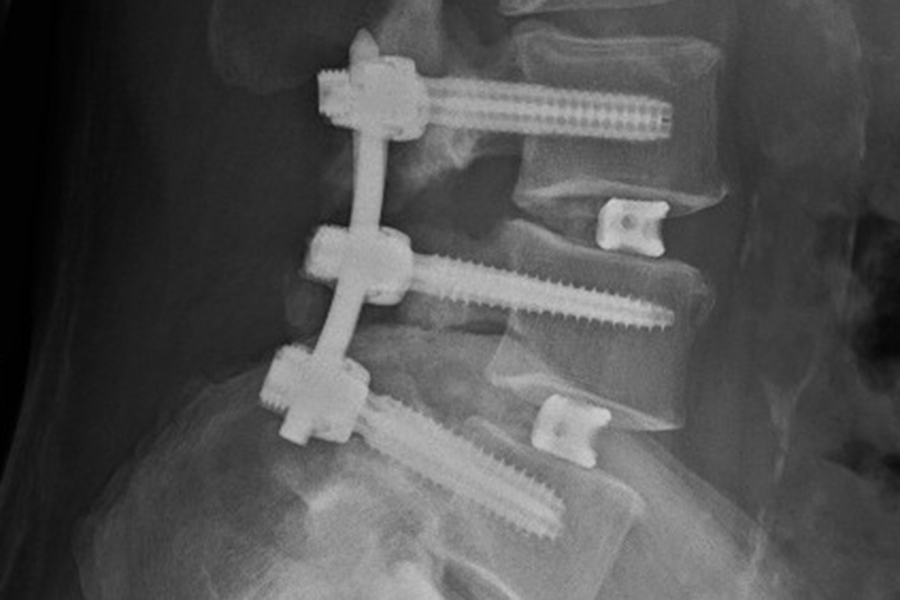

Nach Operation und Stabilisierung eines Wirbelgleitens und einer Verengung des Spinalkanals.

Nach Operation und Stabilisierung eines Wirbelgleitens und einer Verengung des Spinalkanals